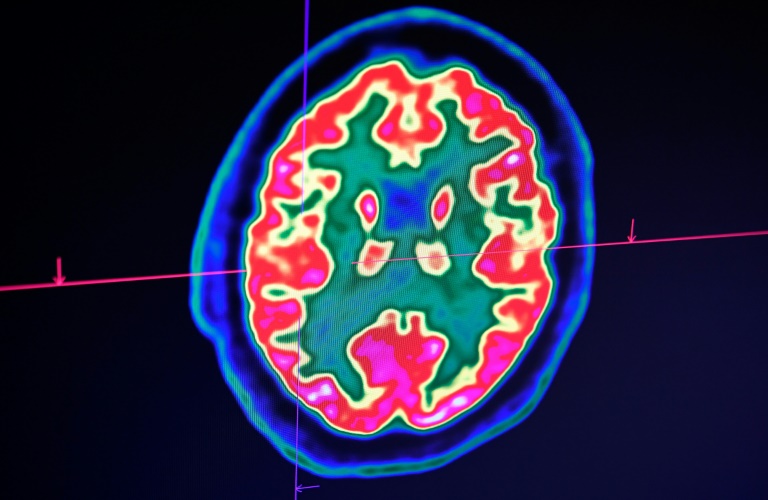

Dans le New England Journal of Medicine, la revue médicale américaine la plus cotée, des médecins français à Strasbourg ont décrit que plus de la moitié de 58 patients en réanimation étaient confus ou agités. Des scanners des cerveaux ont révélé de possibles inflammations.

Il a souffert de confusion et de convulsions et l'imagerie de son cerveau montrait des inflammations. Mais le test n'est pas encore validé et les scientifiques restent prudents.

Ils veulent aussi prélever le liquide cérébrospinal d'un quinquagénaire dont la matière blanche du cerveau est gravement affectée. Mais ces prélèvements, tout comme les IRM, sont difficiles à faire sur des patients sous respirateur artificiel. Et comme la majorité meurt, on étudie mal les dommages neurologiques.